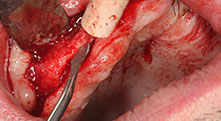

Could you describe briefly, for example, your procedure for mobilizing bone blocks for transplantation?

Bratu: We prefer to harvest bone from the external oblique ridge of the posterior mandible, not from the interforaminal region. After the soft-tissue incision, we use the new saws to define the amount of bone to harvest. With this approach, we also use them for the entire preparation in almost 80% of cases. We may also use other piezo instruments and then at the end a chisel to mobilize the block. We find that this is a very effective surgical technique.

Bratu: We like to use the sandwich technique for augmentation in the lateral mandible. A bone cover is prepared with the piezo saw and the crestal fragment is fixed with microscrews. We place a mixture of autologous bone and xenogenic bone replacement material in between. This works very reliably. You should always ensure sufficiently dimensioned vertical cuts when splitting the alveolar ridge in the mandible. Otherwise the bone may fracture easily.